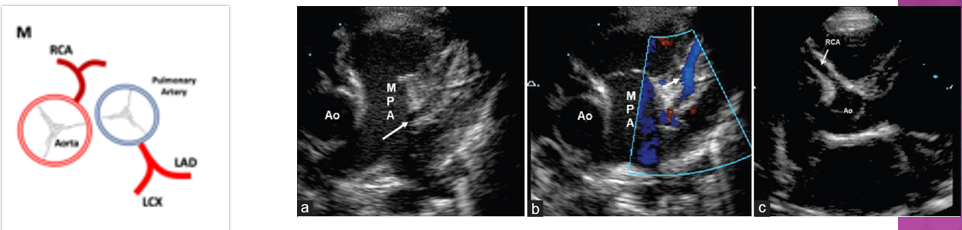

the left main coronary artery arises from

left ao sinus of valsalva

the left main coronary artery branches into

LAD

circumflex

the right coronary artery arises from

the right ao sinus of valsalva

what are the types of anomalous coronary arteries?

left coronary artery arising off the right coronary sinus

right coronary artery arising off the left coronary sinus

anomalous left coronary artery arising off the pulm artery (ALCAPA)